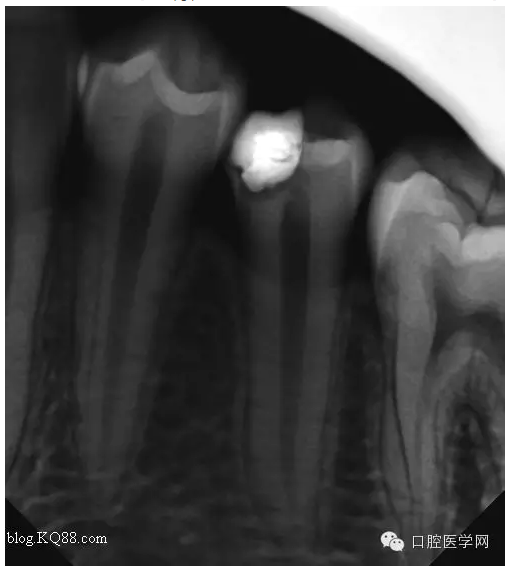

三個月后復(fù)查:高聳的髓角消失。形成約1mm的修復(fù)性牙本質(zhì)?;佳罒o癥狀,溫度測試同對照牙。此時修復(fù)性牙本質(zhì)的形成已趨于穩(wěn)定。每次復(fù)查的溫度測試是判斷牙髓活力,有時雖然沒有臨床癥狀,但牙髓受到慢性刺激會無痛性漸進性壞死。導(dǎo)致保存活髓失敗。

所以每次復(fù)查的溫度測試必不可少的。

最后的充填我是這樣做的:去除部分暫封物。直接樹脂充填。